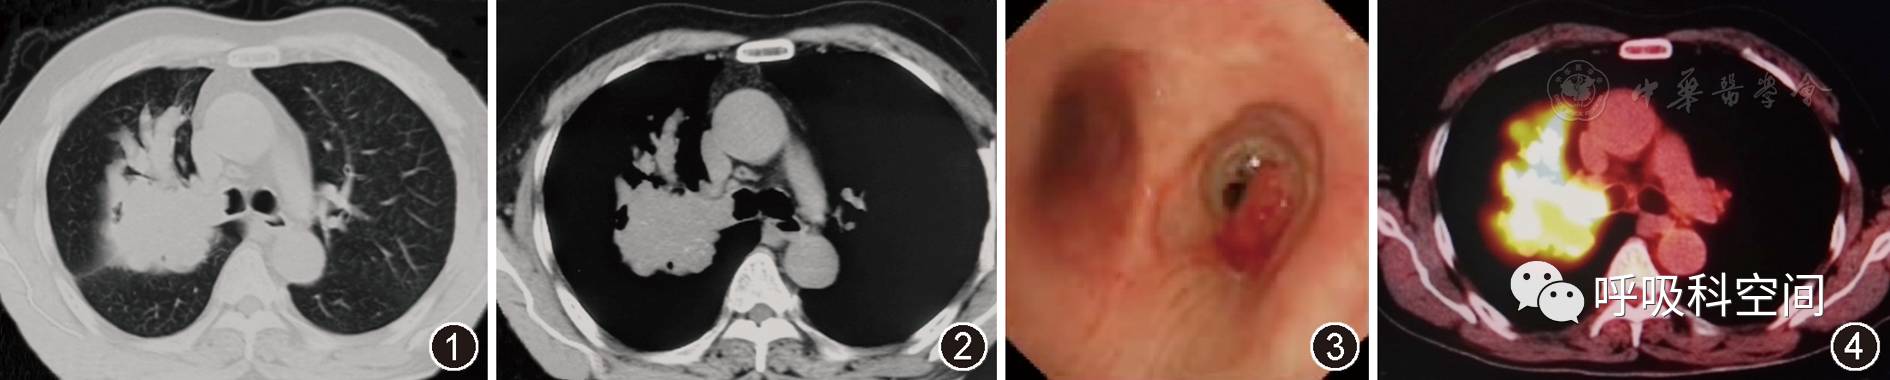

2015年12月15日胸部CT平扫肺窗(图1) 示右肺上叶团块状高密度影,边缘不规整,病变沿支气管分布,右上叶前段支气管扩张,呈"指套征"。右肺上叶支气管闭塞,右主支气管管腔内可见结节样突起。纵隔窗(图2) 示肿块内局部可见多发点状钙化影,"指套"近端呈软组织密度影(47 HU),远端为黏液嵌塞密度影(25 HU)

支气管镜示右主支气管外侧壁可见息肉样新生物生长,表面血运丰富,致右上叶支气管开口闭塞、右主支气管管腔明显狭窄

PET/CT示右肺上叶肿块影,放射性摄取明显增高,最大SUV值约13.5,考虑恶性病变